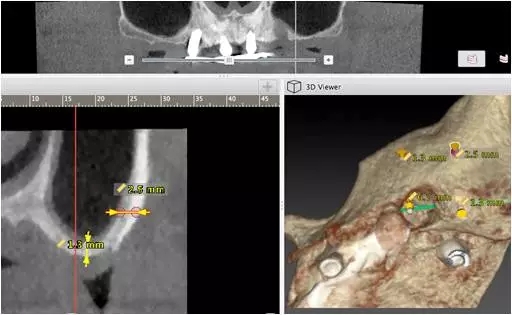

10個月后出現(xiàn)左上頜咬合痛,X線檢查發(fā)現(xiàn)上頜左側(cè)前磨牙區(qū)傾斜種植體周圍低密度影,臨床檢查種植體松動,其余種植體骨結(jié)合良好,遂拔除該種植體(圖3-4)。愈合3個月,CBCT片顯示:25區(qū)種植窩空虛(圖5),愈合不佳,26區(qū)竇底剩余骨高度不足2mm(圖6),其余種植體骨愈合良好,15區(qū)傾斜種植體邊緣骨疑似吸收至第三螺紋(結(jié)合全景片)?;颊咭蠊潭ㄐ迯?fù)。

圖5

圖6